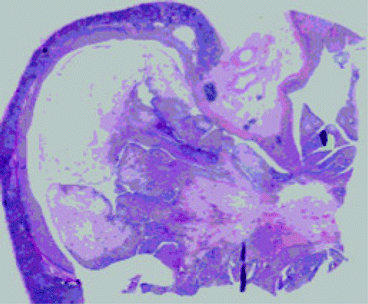

Pdf Congenital Mesoblastic Nephroma Presenting With Neonatal Hypertension